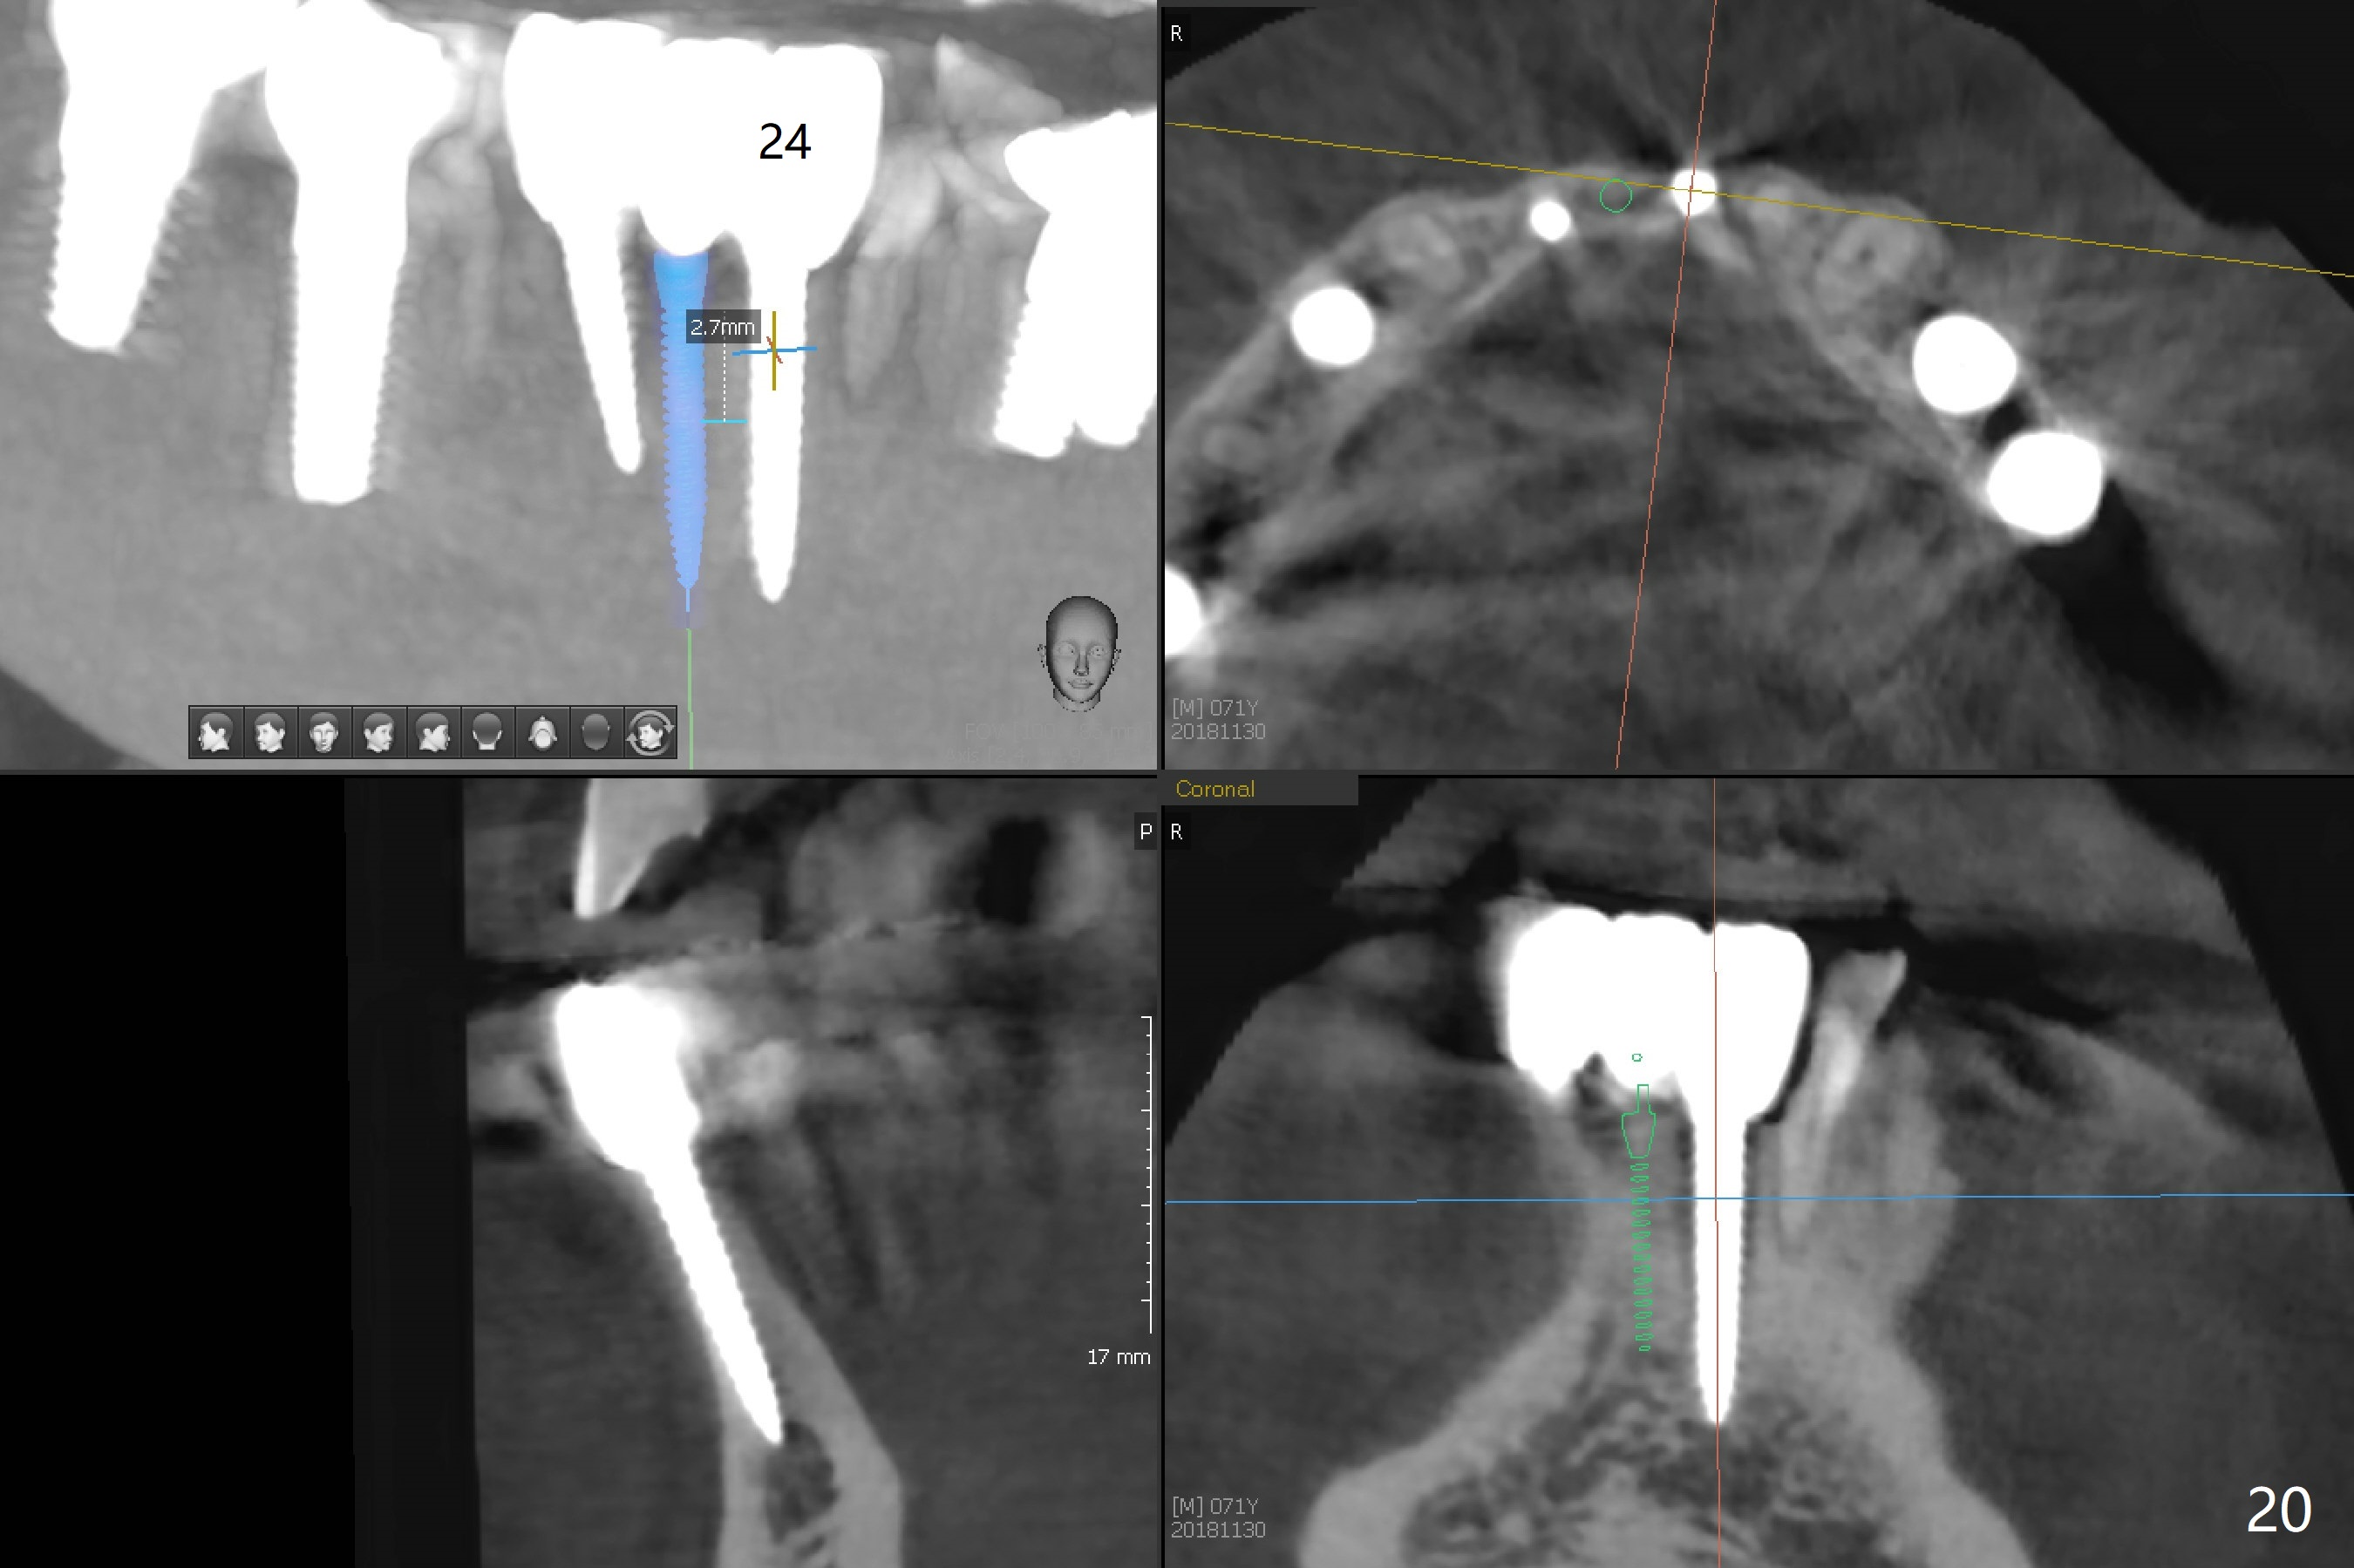

The infection persists at #26 four years 8 months post cementation (Fig.16 *). CBCT is taken. In fact the implant at #26 was placed lingual (Fig.17), while that at #24 buccal (Fig.20). The 2nd option is to remove the implant at #26 and place a 2 mm one at #25 (Fig.18,19). Fabricate a 3-unit cantilever FPD. Take 5x5 cm CT with 1.2 mm drill in place for 10 mm. Change the trajectory and position if necessary.